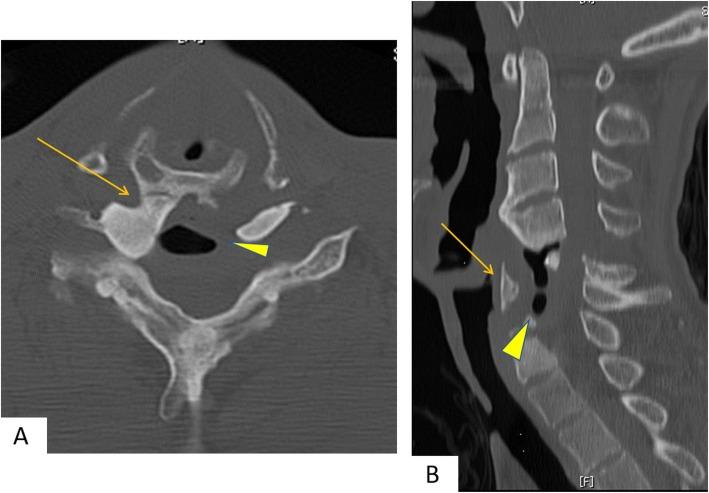

We present a case of a 39-year-old man who had sustained complex spine trauma at C5-6 associated with complete spinal cord injury at the age of 22; the patient presented with a 5-year history of chronic dysphagia. Computed tomography demonstrated posterior shift of the esophagus as well as calcification of the cricoid cartilage and its fusion to the right anterior tubercle of the C5 vertebra. A barium swallow study demonstrated significant barium aspiration into the airway and no laryngeal elevation. The patient underwent resection of the bony bridge and omohyoid muscle flap insertion. His symptoms ameliorated after surgery.